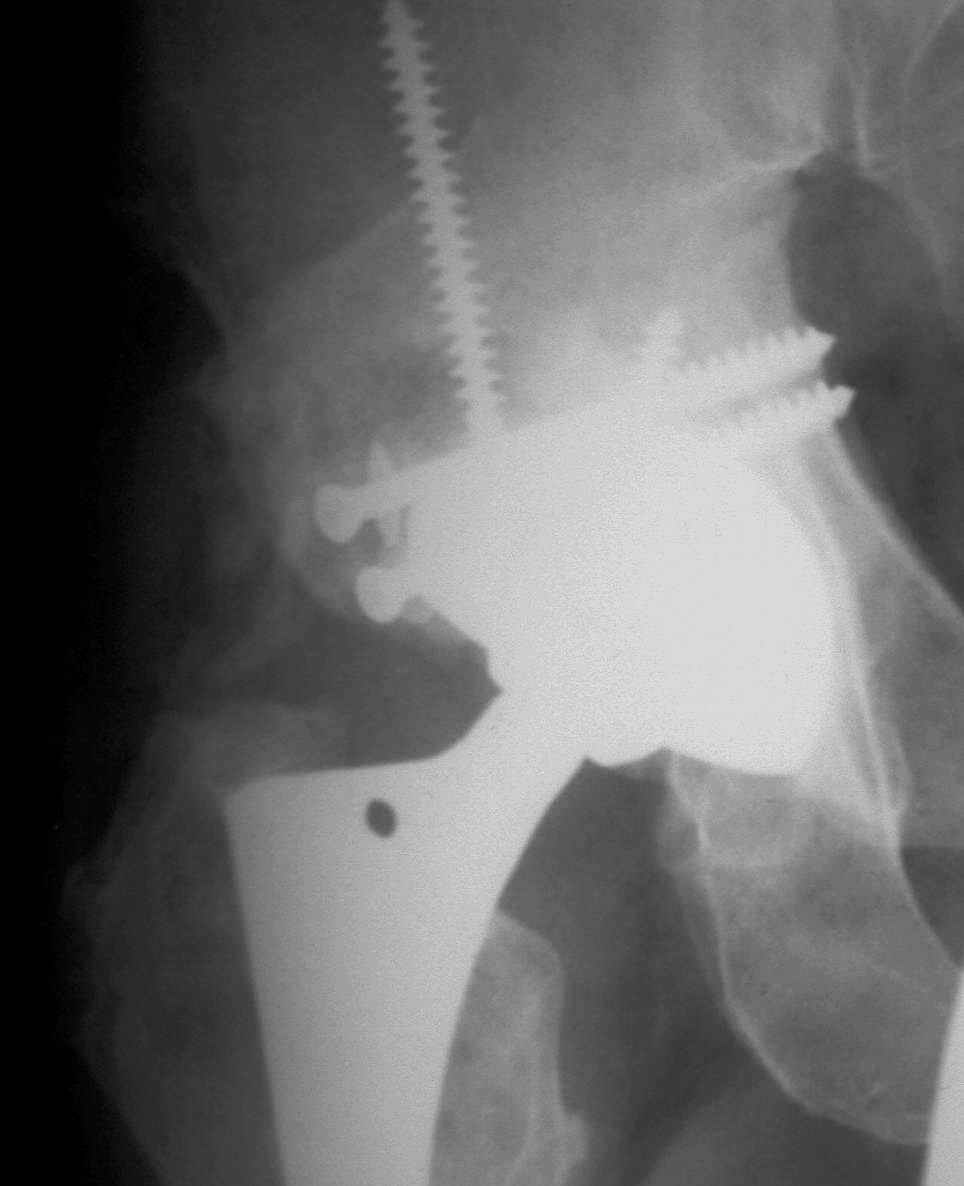

В институте совместно с фирмой Зиммер достаточно регулярно (практически ежемесячно) проводятся 2-х недельные циклы по различным вопросам эндопротезирования. Если есть возможность и желание, мы готовы поделиться с Вами нашим опытом, тем более есть что показать и что обсудить - в настоящее время ежедневно выполняется от 6 до 10 эндопротезирований коленного и тазобедренного сустава. В качестве примеров хочу показать 2 наблюдения, через 1 год и 5 лет после операции

5 лет